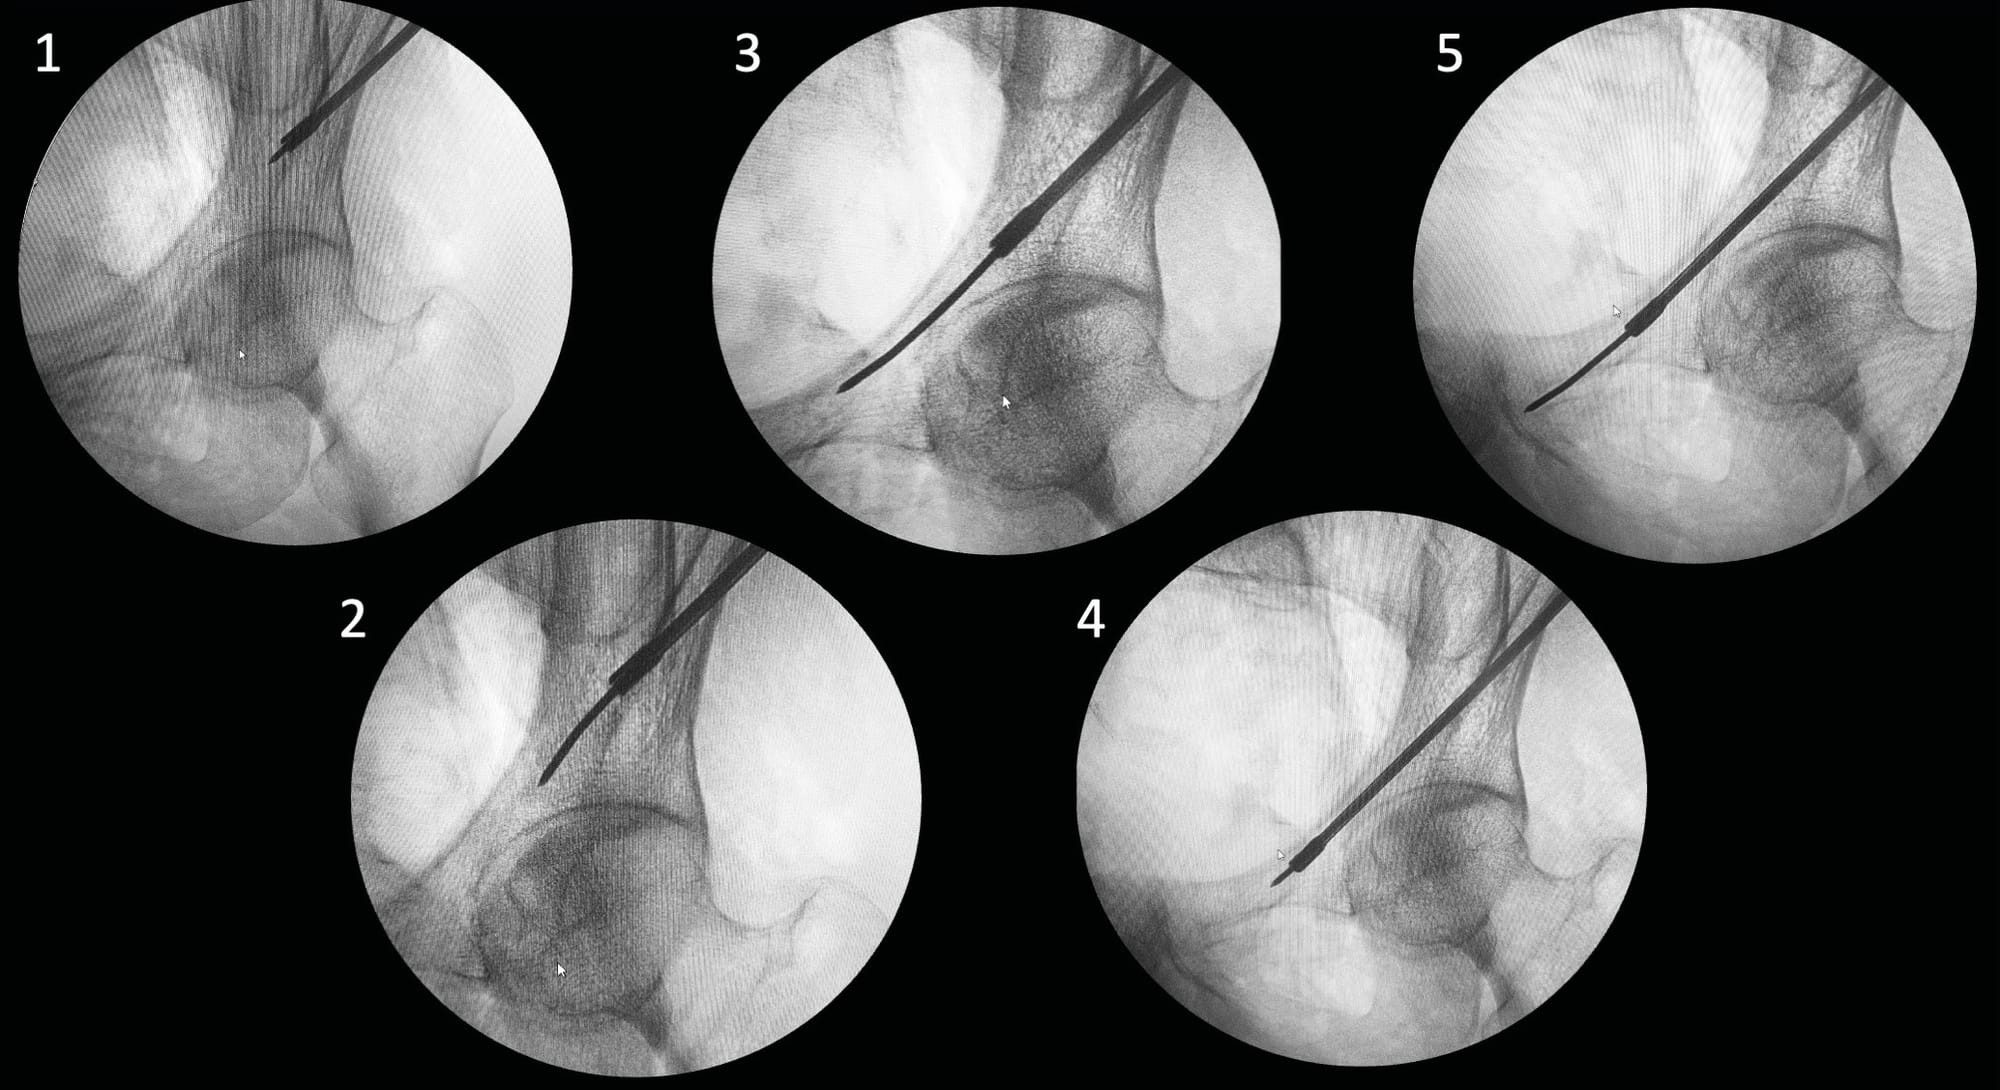

These techniques can be performed in either supine or prone position; however, to minimize anesthetic complications in trauma patients, the supine position is preferred. The starting point for screw placement can be determined using a lateral view. The main fluoroscopic views used are the Inlet and Outlet views. The Inlet view shows the anteroposterior boundaries, while the Outlet view guides the caudocranial trajectory. A lateral view can be used for the entry point, but primarily to secure the trajectory in relation to the lumbosacral trunk. Finally, an Inlet + Obturator view will allow monitoring of the external table of the tuberosity and thus the length and application of the screws. (Figure 3)

For a unilateral IS screw, the starting point is slightly more posterior, with a trajectory directed upward and forward into the sacral promontory (Figure 6). A TS screw will have a more anterior entry point and a horizontal trajectory, thus allowing passage under the sacral wings and above the first foramen for a TS-S1 screw, and between the S1 and S2 foramina for a TS-S2 screw (Figure 7).

Once the appropriate direction is identified, the guide wire is advanced using power equipment. When its tip reaches the level of the foramina, the lateral view allows verification that the wire is positioned posterior to the cortical density lines, thus limiting the risk of misplacement at this level that could lead to iatrogenic injuries of the lumbosacral trunk. Similarly, along with the Inlet view, it helps ensure that the wire trajectory is not directed toward the spinal canal, which could cause cauda equina injuries. It is also recommended to maintain distance from the inferior aspect of the sacral foramina and anterior sacral landmarks. The guide wire is then advanced to the desired position. After checking the different views, the appropriate screw (usually 7.3 or 8 mm in diameter) is implanted using dedicated instrumentation. To improve fixation in the sacral wings, which often have poor bone quality, we prefer using fully threaded screws for all lesions. In cases of sacroiliac disruption, using a lag screw technique allows for compression [14] Maher M, Baldini TH, Parry JA, Mauffrey C. The potential biomechanical advantage of lag by technique screw fixation of the posterior pelvic ring. Eur J Orthop Surg Traumatol 2020;30:1045–8. https://doi.org/10.1007/s00590-020-02665-8. (Figure 4). The screw length can be verified using an ipsilateral and contralateral sacroiliac joint view (Inlet + three-quarter obturator).